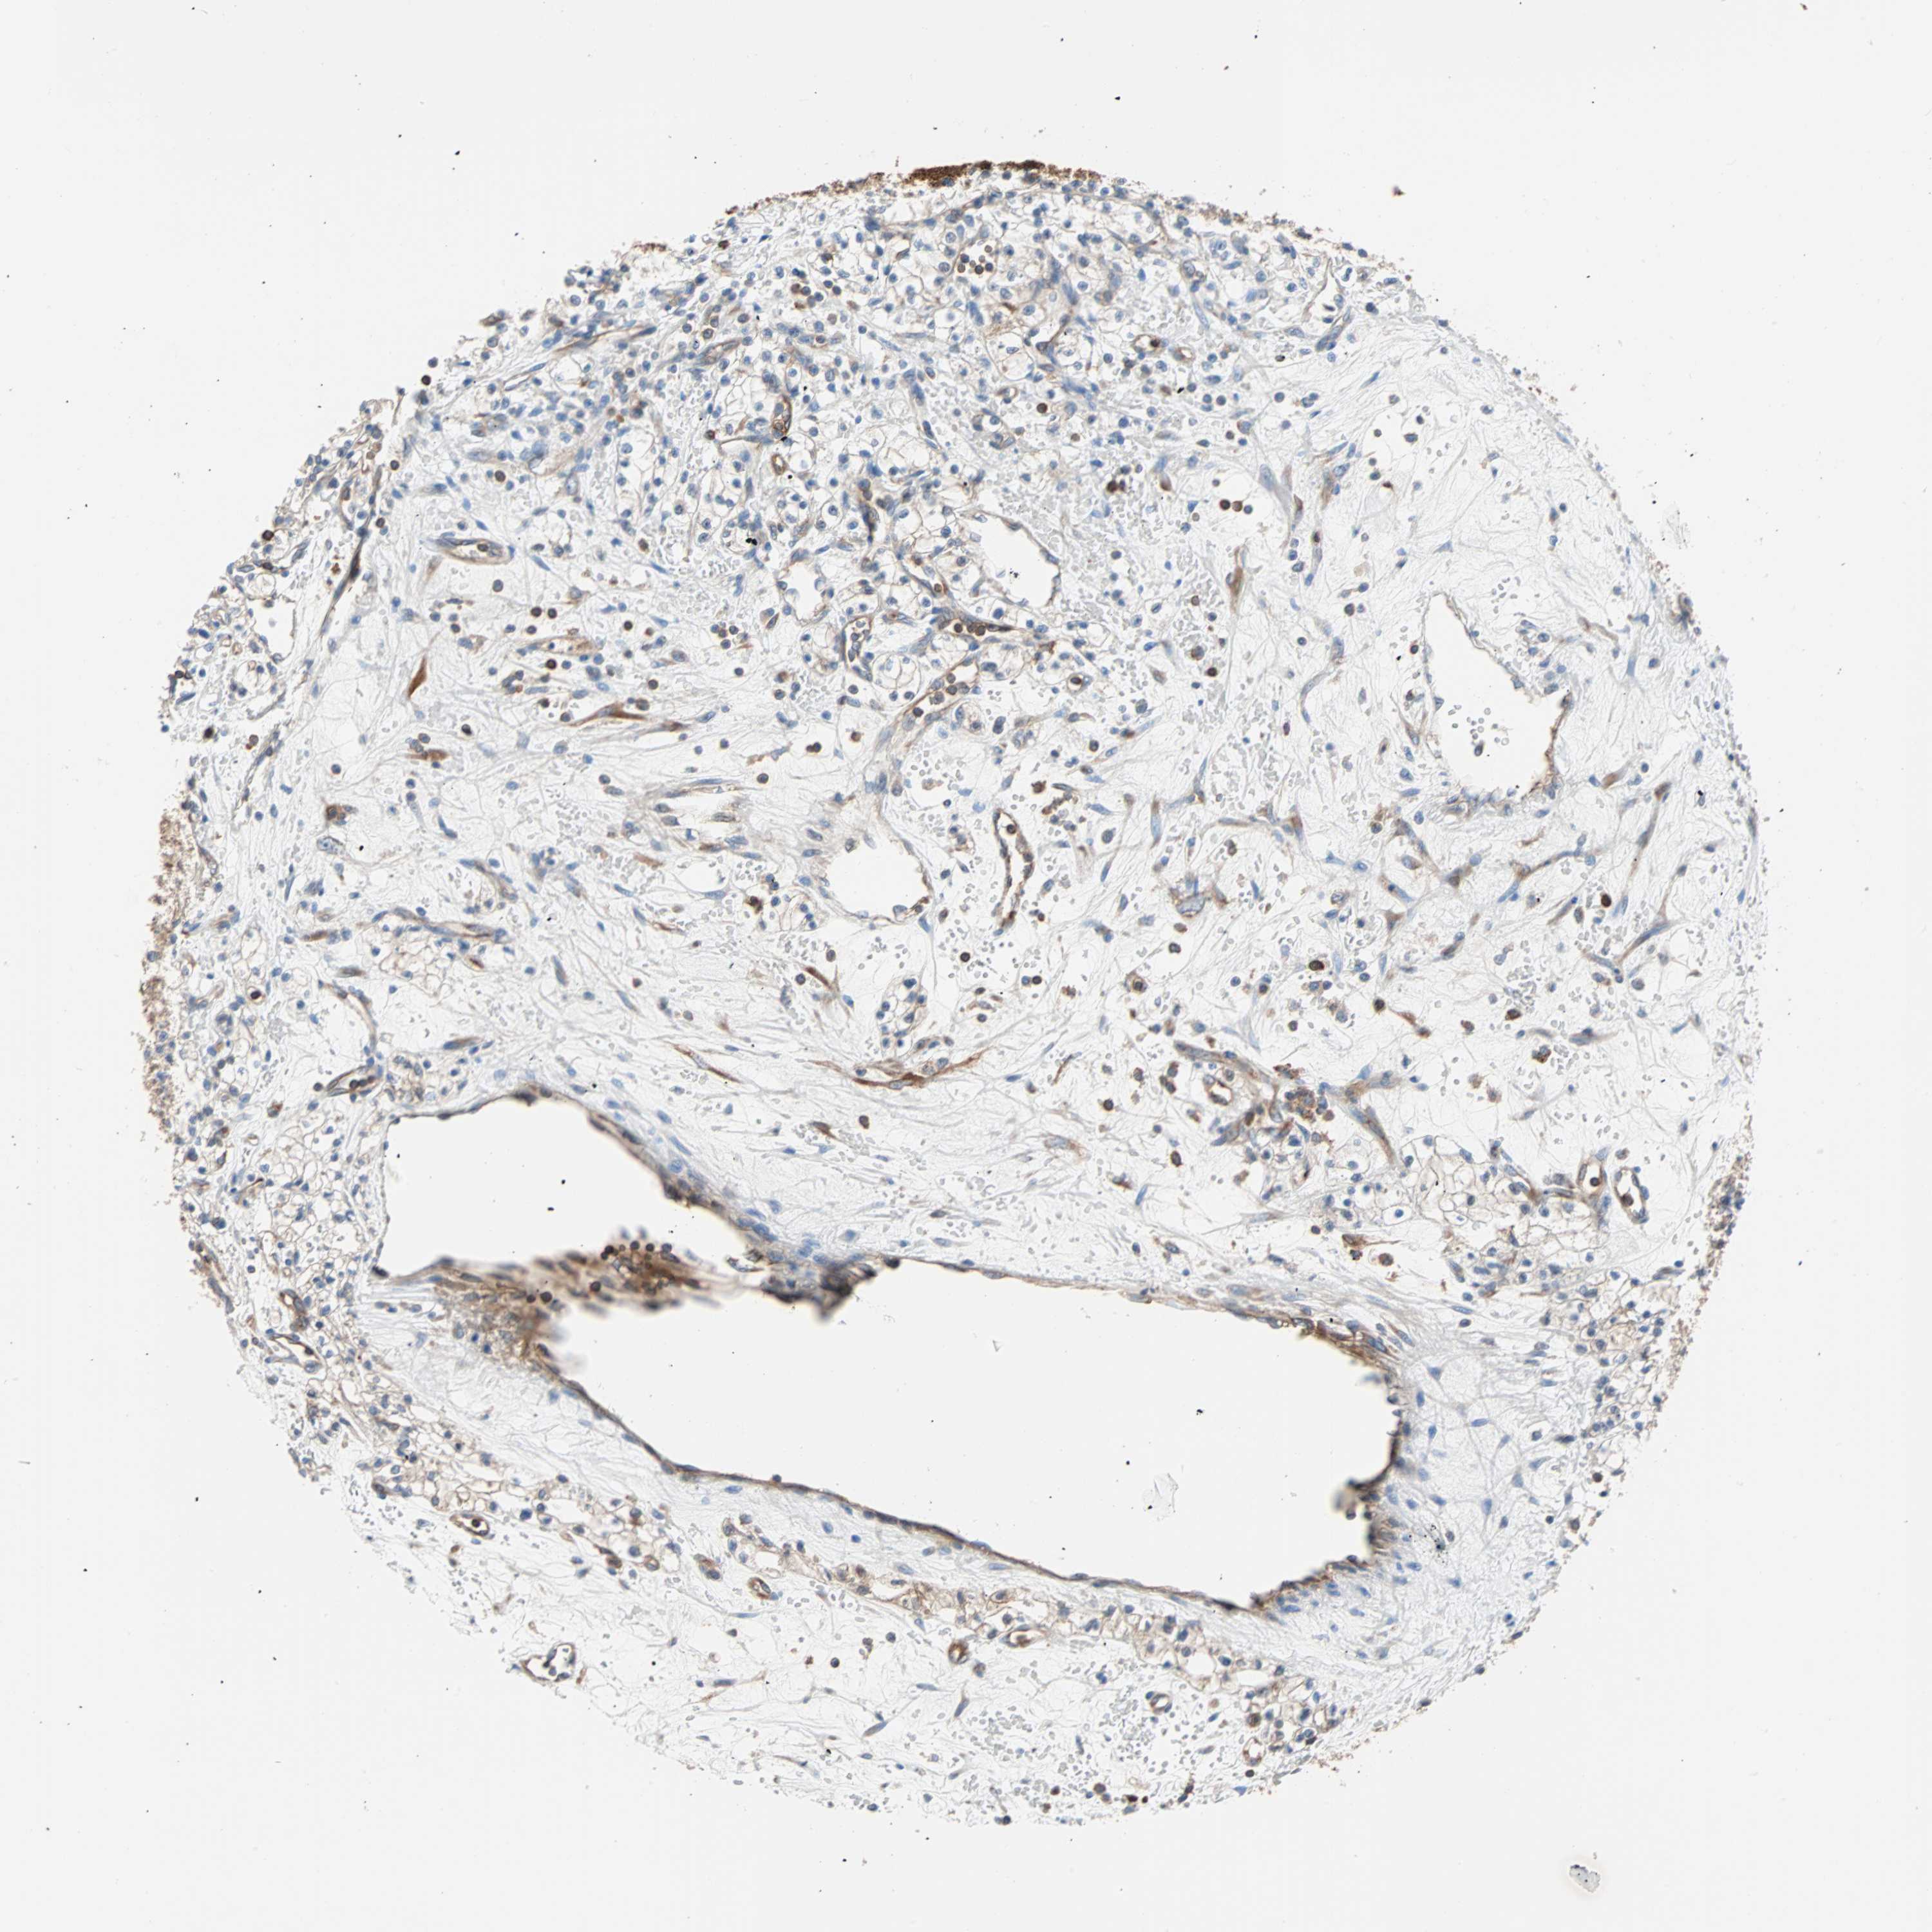

KIDNEY RENAL CLEAR CELL CARCINOMA (TCGA) - Interactive survival scatter ploti

The Survival Scatter plot shows the clinical status (i.e. dead or alive) for all individuals in the patient cohort, based on the same data that underlies the corresponding Kaplan-Meier plots. Patients that are alive at last time for follow-up are shown in blue and patients who have died during the study are shown in red.

The x-axis shows the expression levels (FPKM) of the investigated gene in the tumor tissue at the time of diagnosis. The y-axis shows the follow-up time after diagnosis (years). Both axes are complimented with kernel density curves demonstrating the data density over the axes. The top density plot shows the expression levels (FPKM) distribution among dead (red) and alive patients (blue). The right density plot shows the data density of the survived years of dead patients with high and low expression levels respectively, stratified using the cutoff indicated by the vertical dashed line through the Survival Scatter plot. This cutoff is automatically defined based on the FPKM cutoff that minimizes the p-score. The cutoff can be changed by dragging the vertical line or by entering a cutoff value in the square labeled "Current cut-off".

Under the Survival Scatter plot the p-score landscape (black curve; left axis) is shown together with dead median separation (red curve; right axis). Dead median separation is the difference in median mRNA expression between patients who have died with high and low expression, respectively. It is calculated as follows: median FPKM expression of dead patients with high expression - median FPKM expression of dead patients with low expression. This is intended to aid the user in visually exploring custom cutoffs and the associated p-scores and dead median separation.

Individual patient data is displayed and can be filtered by clicking on one or more of the category buttons on the top of the page. Categories describing expression level and patient information include: high, low, alive, dead, female, male and tumor stages. The scale of the x-axis can be toggled between linear and log-scale by clicking on the "x log" button. Mouse-over function shows TCGA ID, patient information and mRNA expression (FPKM) for each patient.

& Survival analysisi

Kaplan-Meier plots summarize results from analysis of correlation between mRNA expression level and patient survival. Patients were divided based on level of expression into one of the two groups "low" (under cut off) or "high" (over cut off). X-axis shows time for survival (years) and y-axis shows the probability of survival, where 1.0 corresponds to 100 percent.

EEF2 is potential prognostic, high expression is favorable in Kidney Renal Clear Cell Carcinoma (TCGA)

Best expression cut offi

Based on the FPKM value of each gene, patients were classified into two groups and association between prognosis (survival) and gene expression (FPKM) was examined. The best expression cut-off refers the FPKM value that yields maximal difference with regard to survival between the two groups at the lowest log-rank P-value. Best expression cut-off was selected based on survival analysis .

When clicking on this number, the vertical dashed line indicating cut-off, the interactive survival plot, and the Kaplan-Meier curve will be adjusted to show results based on the best expression cut-off.

: 1069.53

TCGA RNA samplesi

RNA-seq data is reported as average FPKM (number Fragments Per Kilobase of exon per Million reads), generated by the The Cancer Genome Atlas (TCGA) .

Normal distribution across the dataset is visualized with box plots, shown as median and 25th and 75th percentiles. Points are displayed as outliers if they are above or below 1.5 times the interquartile range. FPKM values of the individual samples are presented next to the box plot.

Average pTPM 1352.9

Number of samples 521